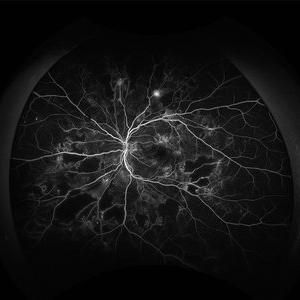

Proliferative Diabetic Retinopathy Angiography

Jan 22 2024 by Selene Rodríguez-Castro, MD

PDR

Photographer: Selene Rodríguez- Castro, APEC

Condition/keywords: background diabetic retinopathy (BDR)